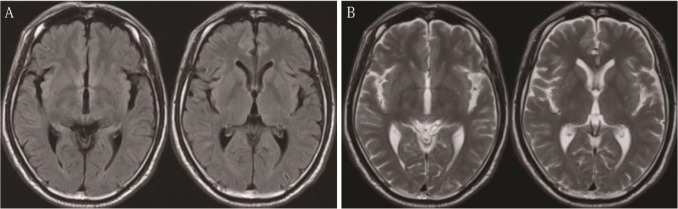

62岁男性,主诉复视病史1个月。60岁时,患者有紧张性头痛,曾行磁共振成像(MRI)检查,未见异常表现(图1)。MRI两年后,患者行计算机断层扫描(CT)和磁共振成像(MRI)检查复视。CT显示肿瘤呈增强形态,直径3cm,松果体区可见钙化(图2A)。肿瘤在t1加权MRI上呈等强度(T1WI,图2B);T2WI微低信号(图2C)和流体衰减反演恢复图像(图2D);T2* WI低信号明显(图2E),扩散WI明显(图2F), T1WI上钆异质增强(图2G)。钆增强T1WI矢状面显示垂体神经区未见肿瘤(图2H)。脑积水是由于肿瘤引起导水管狭窄所致。病人转到我们医院治疗。入院后复视好转,眼球运动充分平稳。经简易心理状态检查和韦氏成人智力量表检查,其心理功能轻度恶化。他的下面血清肿瘤标记物在正常范围:甲胎蛋白,β人体绒毛膜促性腺激素(βhcg)、癌胚抗原、β2-microglobulin,促黄体激素5.2个人/毫升(参考价值:1.7 - -11.2)、促卵泡激素9.2个人/毫升(参考价值:2.1 - -18.6),和睾酮482.0毫微克/分升(参考价值:220.9 - -715.8)。脑血管摄影显示一个微弱的肿瘤染色没有任何动静脉分流。CT检查未发现有转移到脑的肿瘤。因此,在鉴别诊断时要考虑多种肿瘤,如松果体实质肿瘤、神经胶质瘤、不明来源的转移性肿瘤和海绵状血管瘤。随后患者行内镜下活检和三脑室造口术,经右额冠状前刺孔及可操作的电视镜检查。肿瘤很容易在松果体区发现一个灰色肿块,包含旧时出血和钙化(图3A),怀疑转移到漏斗部(图3B)。活检标本取自几个不同的部位。活检时肿瘤有少量出血,冲洗可轻易止血。术后无并发症发生。术中脑脊液(CSF)β-HCG为0.12 mIU/mL,略升高。脑脊液中未检测到肿瘤细胞。组织病理学上,肿瘤呈2细胞型,上皮样细胞大,淋巴细胞小。前一个细胞经胎盘碱性磷酸酶(图4C)和c-kit(图4D)染色呈阳性。未观察到其他GCT成分。因此,此肿瘤的组织病理学诊断证实为纯生殖细胞瘤。患者接受单剂量放射治疗:脑室播散小剂量预防照射(25.2 Gy),原发肿瘤部位放射增强(25.2 Gy), MRI未见脊髓播散征象。放疗后肿瘤完全消失,无神经功能缺损。脑脊液β-HCG水平恢复正常。经过4年的放射治疗后,连续的MRI随访研究和β-HCG检测没有发现肿瘤复发。

图1:入院前2年进行磁共振成像。注意,在液体衰减反转恢复图像(A)或t2加权图像(B)上,松果体区未见肿瘤。